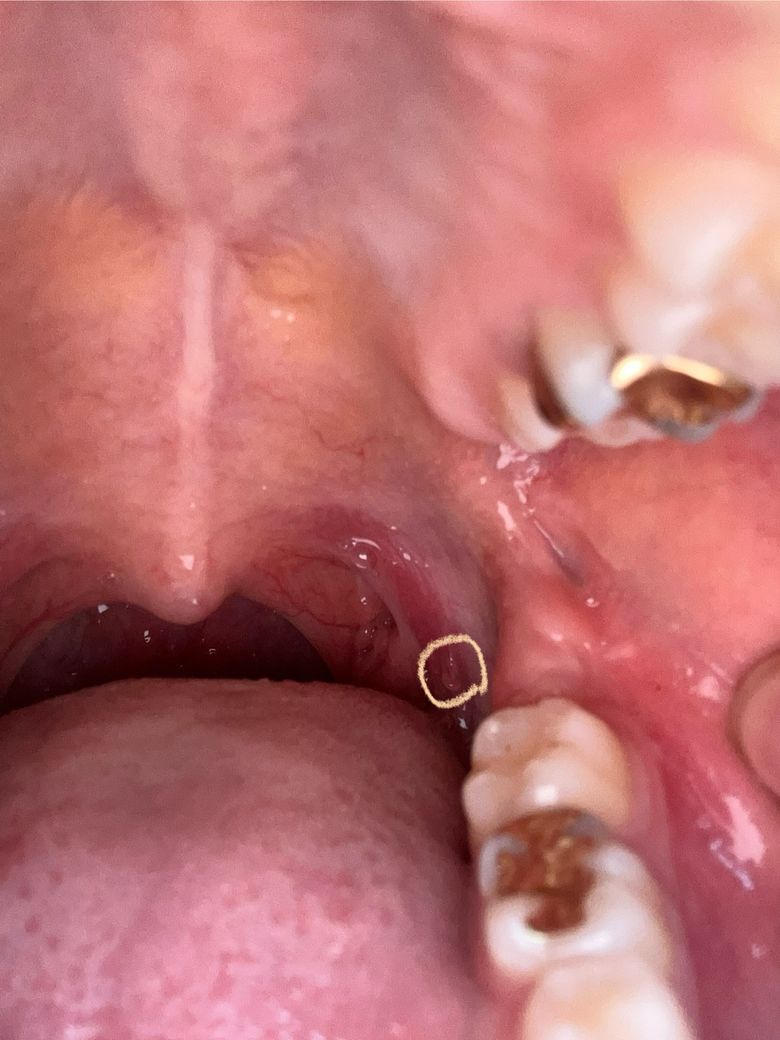

구개설궁쪽에 살같은게 튀어나와있어요 편평유두종인가요?

동그랗게 친 부분이 점막이 동그랗게 튀어나온것처럼 되어있는데 편평유두종인가요? 좀 혀에 있는 설편도..?같은 성곽유두인가 그런거랑 비슷하게 생겼어요 이게 뭔가요?

부위도 그렇고 생김새가 편평유두종의 가능성도 있어보입니다 구강내과나 이비인후과가서 조직검사 받아보시기 바랍니다